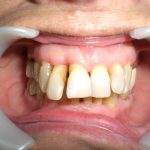

Arcade maxillaire avant traitement orthodontique, séquelles de maladie parodontale